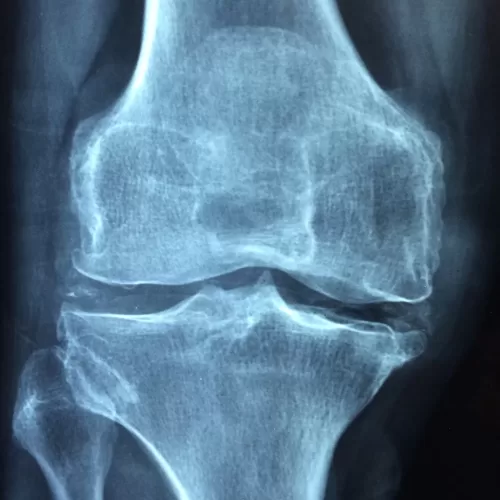

“This study revealed that both acupuncture and physiotherapy improved the clinical symptoms of pain, morning stiffness and joint dysfunction. However, acupuncture treatment showed better curative effect than physiotherapy, suggesting that acupuncture may be a superior non-operative treatment for KOA [knee osteoarthritis] compared with physiotherapy.”

Osteoarthritis is a type of arthritis where the bone, cartilage and synovium wear down, leading to pain and stiffness. Synovium lines the joints and produces synovial fluid that lubricates the joins as well as supplies them with nutrients and oxygen. A 2016 study from the American Journal of Translational Research compared the effectiveness of acupuncture and physiotherapy for treating knee osteoarthritis. When looking at motor scores, pain, stiffness and physical function, those patients who received acupuncture had significantly improved scores compared to patients who received physiotherapy.